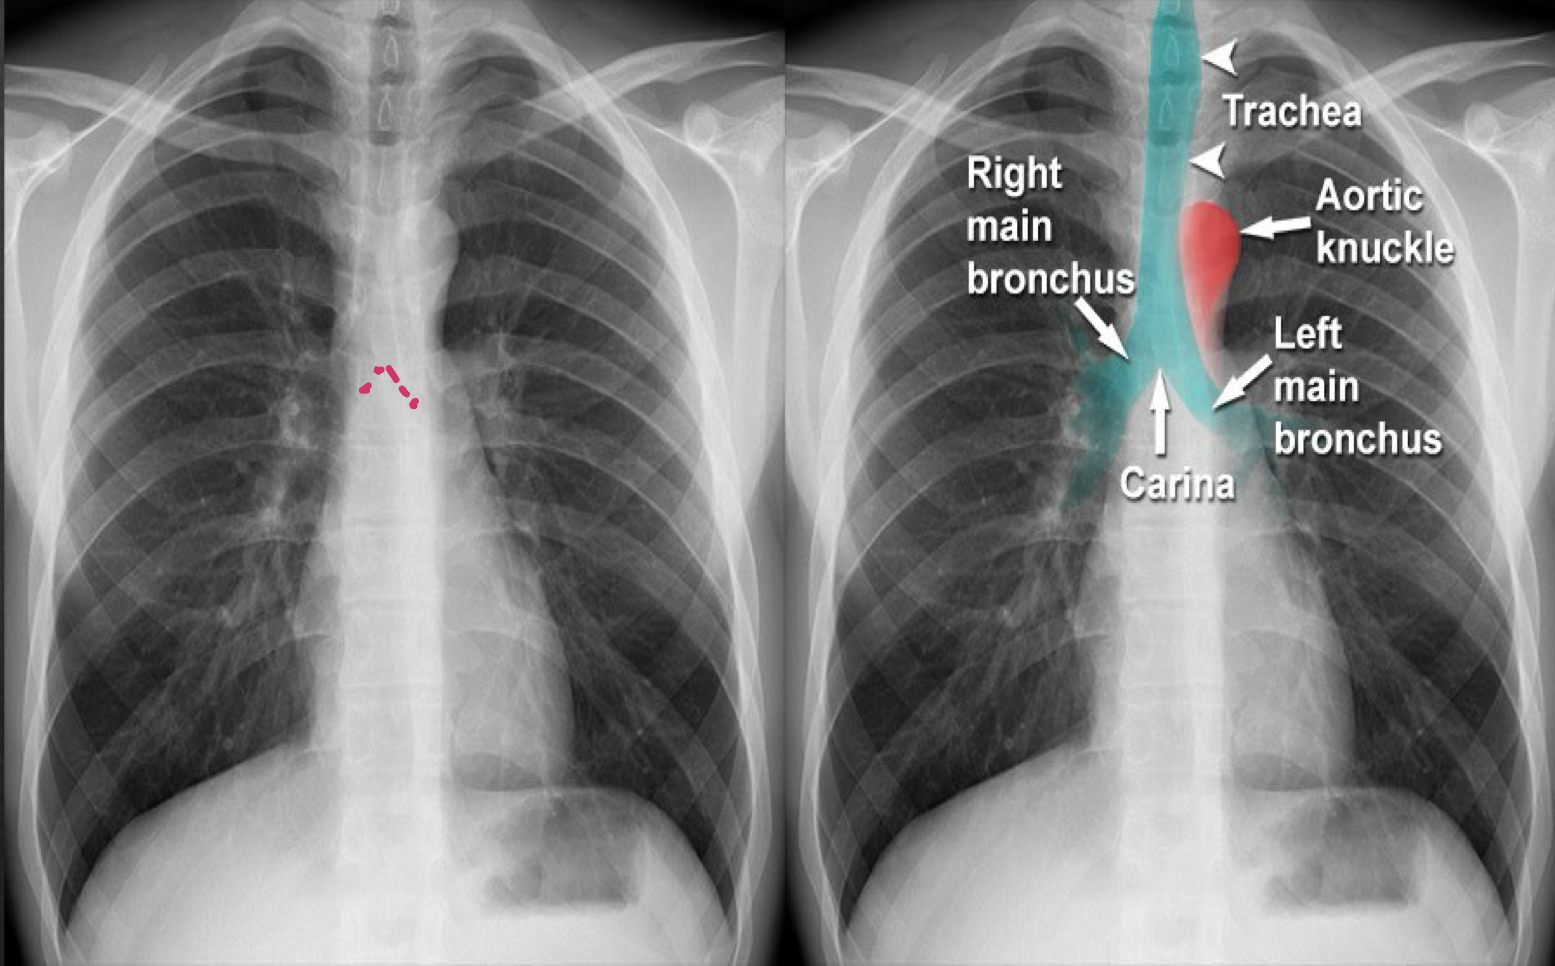

airway (frontal)

trachea: look for deviation other than aortic knob

bronchi: should be visible

carina: should be visible

cardio anatomy: frontal view

ascending aorta: shoudl not project more lateral than the RA

aortic knob: will normally push trachea slightly to right

right atria: should project more lateral than ascending aorta

left atria: doe snot contribute to border of heart unless pt is rotated

left ventricle: should not show significant enlargement

descending aorta: parallels spine and barely visible